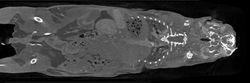

小鼠腰椎骨Micro-CT掃描

骨骼。骨骼是 Micro-CT 最主要的套用領域之一,其中骨小梁又是主要研究對象。骨松質和骨皮質的變化與骨質疏鬆、骨折、骨關節炎、局部缺血和遺傳疾病等病症有關。目前,Micro-CT 技術在很大程度上取代了破壞性的組織形態計量學方法,目前中科愷盛的Micro-CT能夠得到16個常用的骨參數,基本上滿足了計量學的的需求。

骨小梁成像材料科學